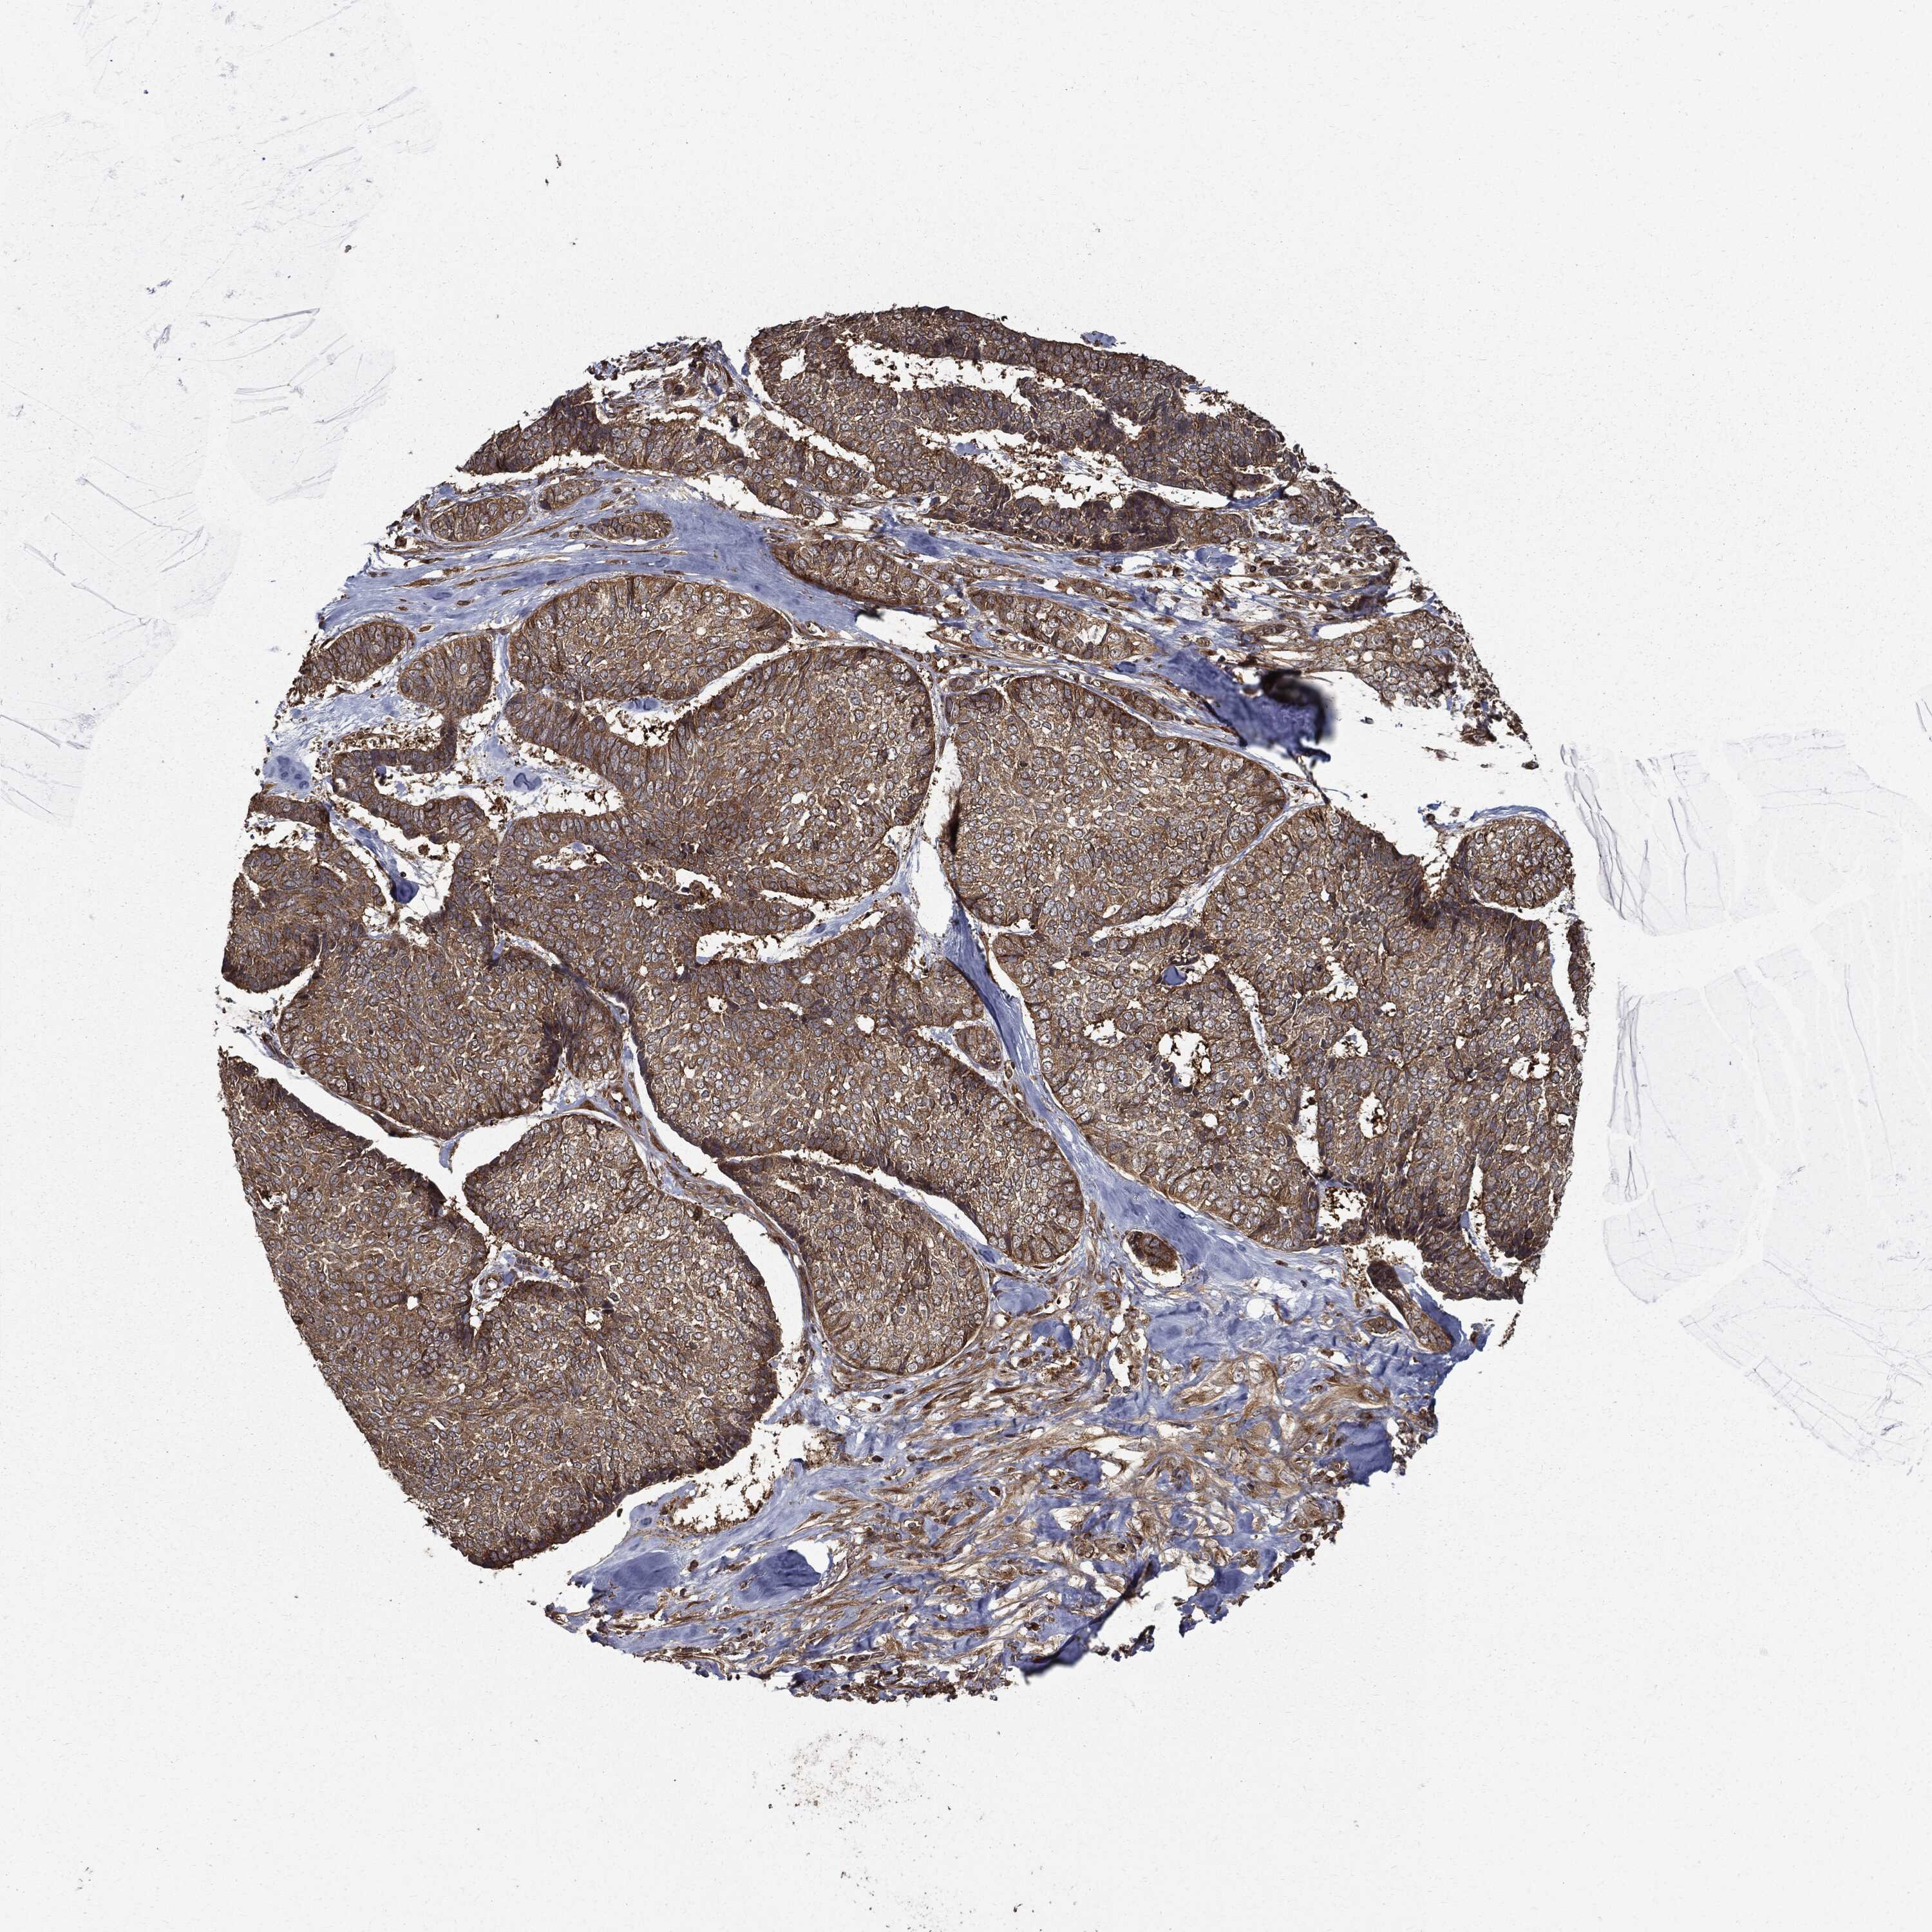

Basal cell and squamous cell cancer

SKIN CANCER - Protein expressioni

A mouse-over function shows sample information and annotation data. Click on an image to view it in a full screen mode. Samples can be filtered based on level of antibody staining by selecting one or several of the following categories: high, medium, low and not detected. The assay and annotation is described here.

Each image is clickable and will lead to virtual microscopy that enables deeper exploration of all samples and also displays staining intensity scores, fraction scores and subcellular localization as well as patient and tissue information for each sample.

Antibody HPA026114

Antibody HPA051524

Antibody CAB002756

Basal cell carcinoma

Squamous cell carcinoma, NOS

Squamous cell carcinoma, metastatic, NOS